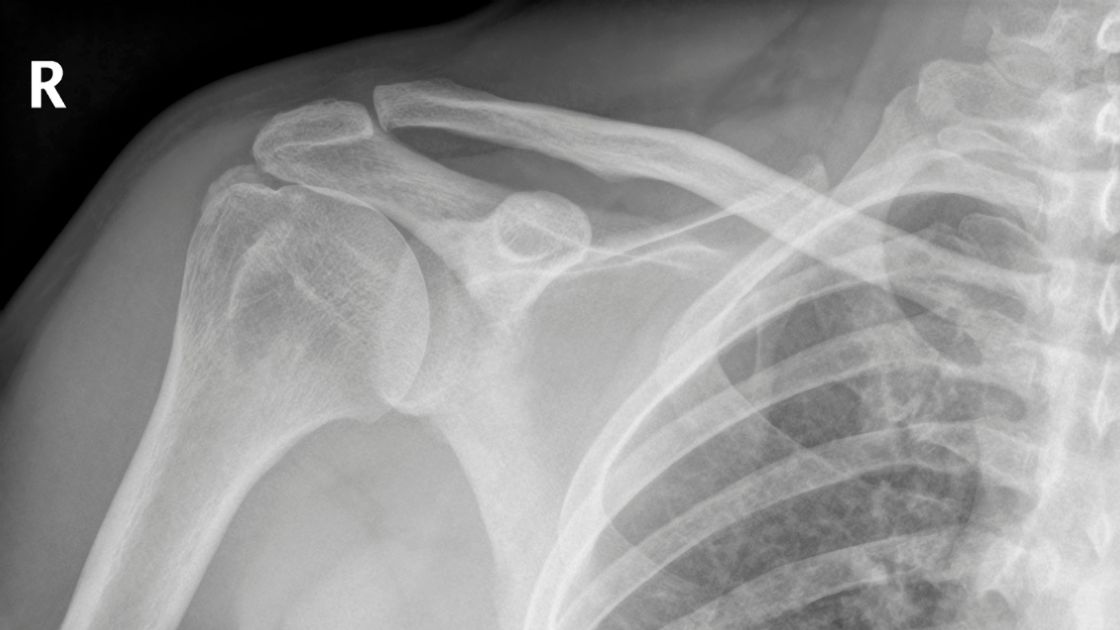

• X-rays: While they can't show soft tissues like tendons, X-rays can reveal bone spurs or other abnormalities affecting the rotator cuff.